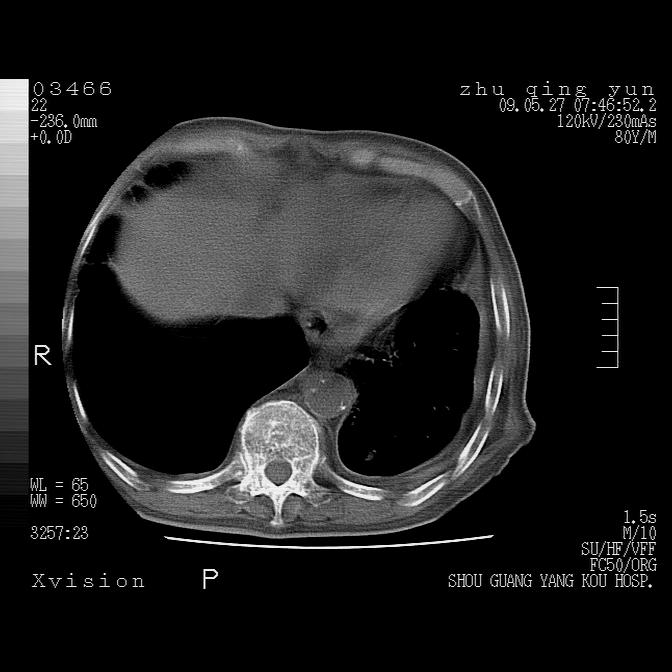

病人男性,年龄80,气喘来院,其他病史不太详细,1月前有过恶心,呕吐,在当地人民医院做过钡餐,诊断胃炎,

1)考虑左肺中央型肺癌并左肺下叶阻塞性肺炎、不张;左胸膜腔积液、心包积液、纵隔淋巴结转移;癌肿累及左心房。2)左心室大。冠状动脉壁钙化斑。

恶性占位是肯定的,并累及心包并纵隔淋巴结转移/左肺癌性淋巴管炎/肺部感染。是中心性或纵隔型肺癌,还是后纵隔恶性占位,还是食道中下段癌或食道受累需鉴别。

支持以上,左肺肿块应该是周围型吧,考虑左下肺周围型肺癌伴肺内转移,阻塞性肺炎,纵隔淋巴转移,左侧胸膜及心包转移